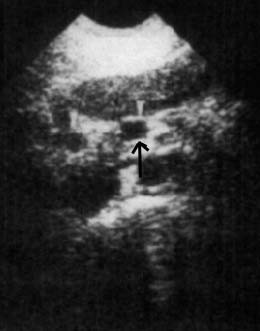

- בבדיקת על-שמע (אולטרה-סאונד) ניתן להדגים גוש בלבלב (תצלום 32.9).